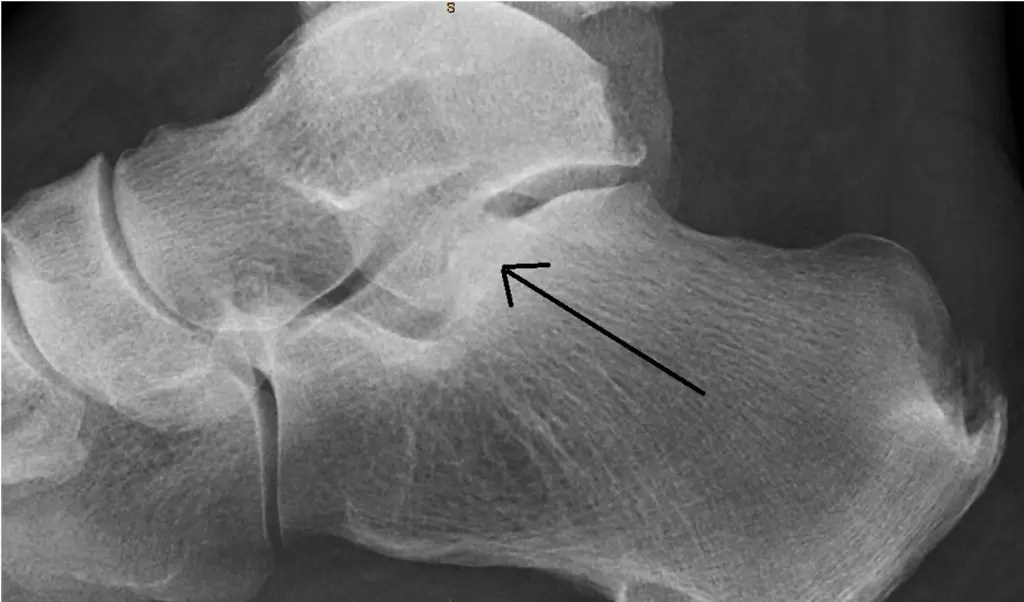

From leonardo-ortho.ch

Osteoarthritis hind foot and mid foot Osteoarthritis Feet Disability If your osteoarthritis is so hard to manage that leaving the workforce is a must, you may qualify for social security disability benefits. For instance, some people may experience mild pain that goes. Foremost, you must meet the following criteria: The ssa has a list of disabling conditions, including rheumatoid. In some cases, these symptoms may make it difficult to. Osteoarthritis Feet Disability.